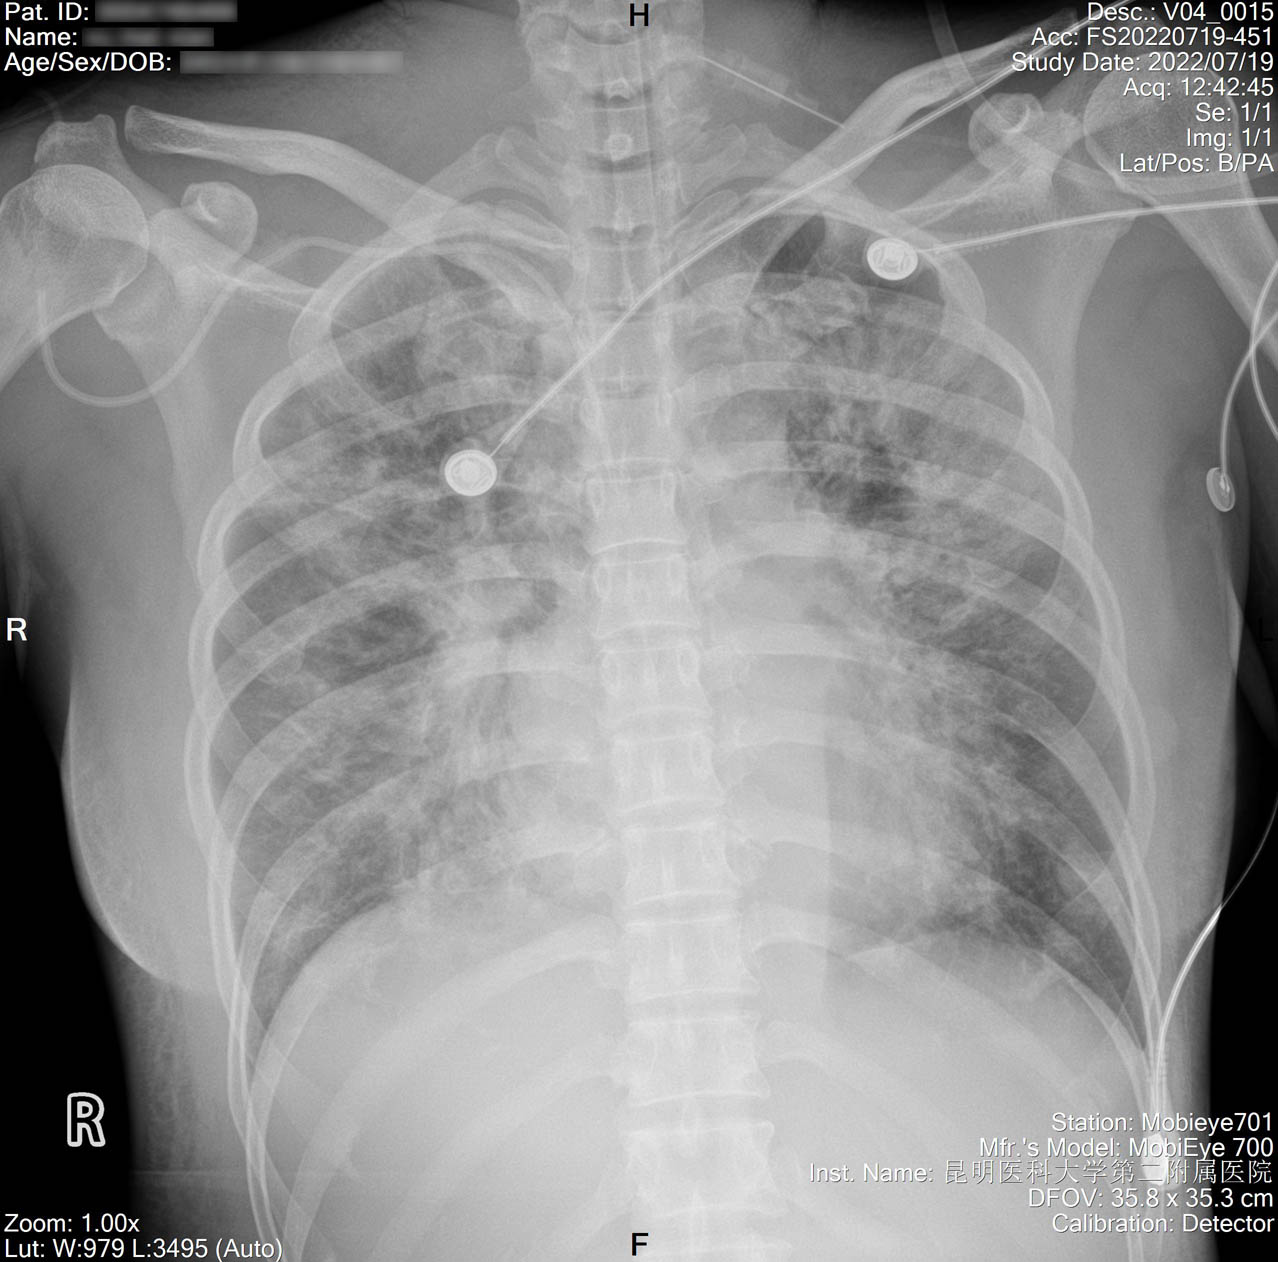

1.2.156.112536.2.560.184134135149163099.1425201816976.4.jpg

2022-07-18_胸片